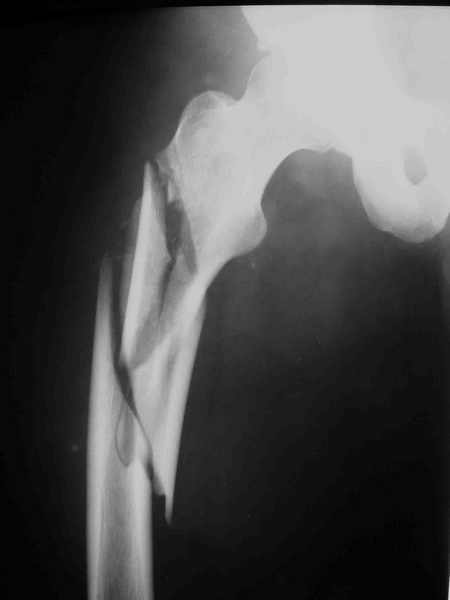

извините за опоздание , вот фотографии

<На R-мме таза ( в прямой проекции, вход и выход из таза) определяется изолированный разрыв лонного сочленения с диастазом 4см,расширение щели правого КПС(вертикальной нестабильности нет, >

В представленном случае повреждение несомненно ротационное и реальный диастаз как раз около пограничных 2,5 см, репозиция идеальная, достигнута в первые дни после травмы. Я бы ограничился 3 мес фиксации в аппарате с ограничением нагрузки первый месяц, и функциональными снимками в 6 -8 недель.